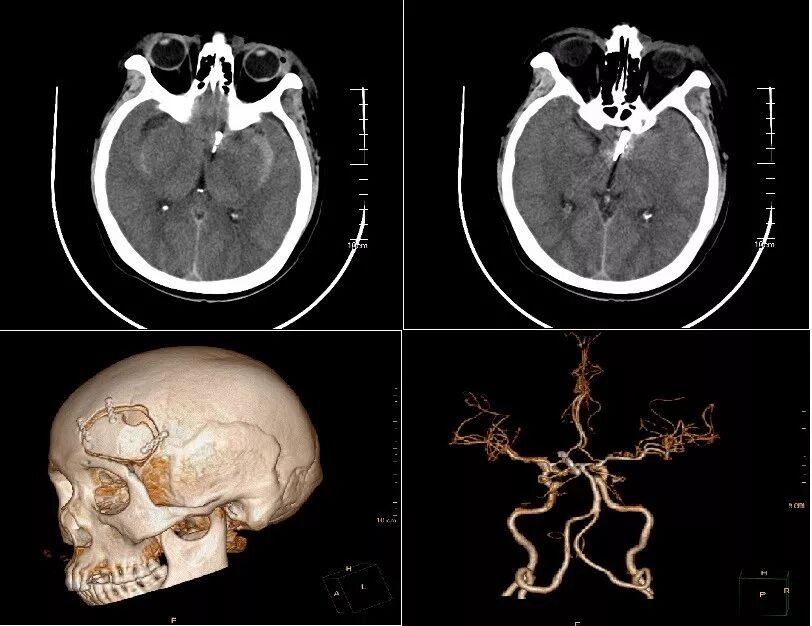

术前CT:脑干周围、双侧侧裂池、后纵裂广泛高密度影,蛛网膜下腔出血。(图2-1)

图2-1. 入院头颅CT检查提示广泛的蛛网膜下腔出血

术前CT:鞍上池及双侧外侧裂见高密度影,蛛网膜下腔出血。(图1)

术前CTA:基底动脉顶端见瘤样突起,大小约0.5×0.8cm;余血管无明显异常。(图2)

图3-1. 患者入院后头颅CT提示蛛网膜下腔出血,以脑干前方为主,提示后循环动脉瘤破裂出血可能。

图3-2. 患者入院后头颅CTA提示基底动脉顶端动脉瘤,大小约0.5×0.8cm。余血管未见明显异常。